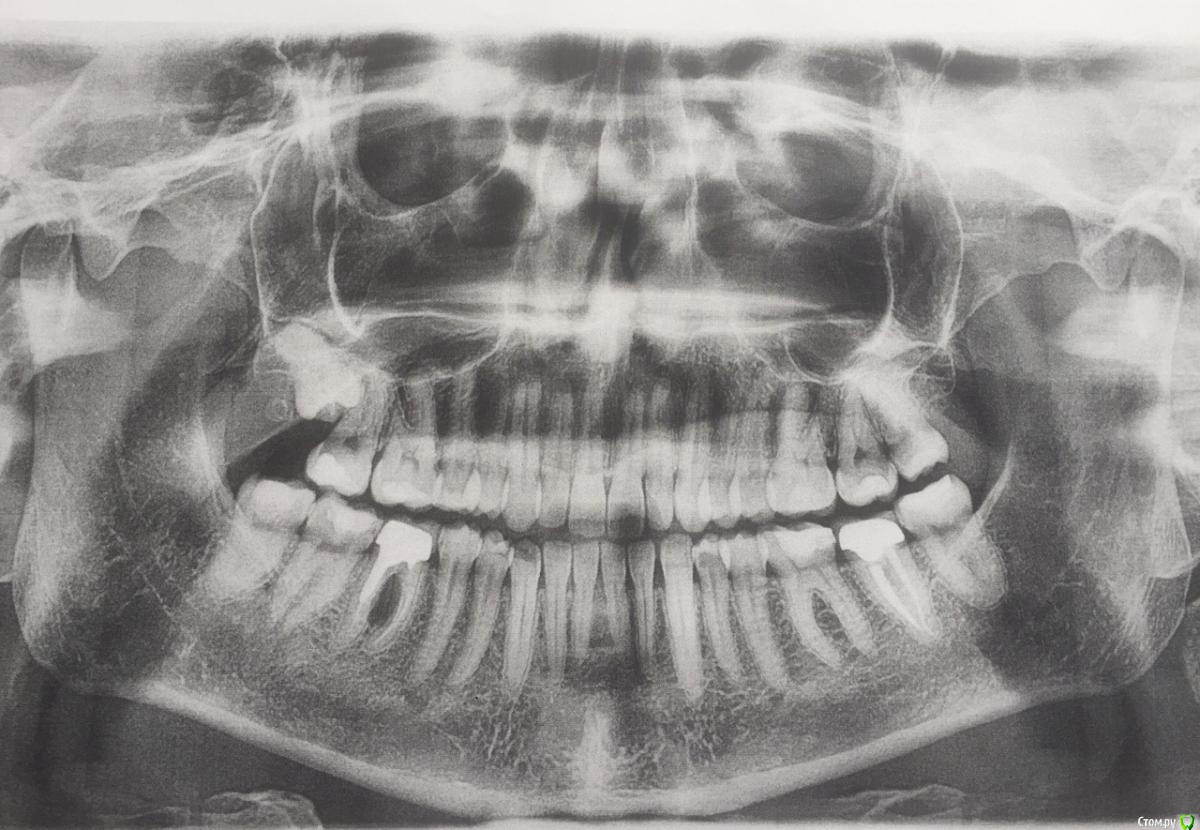

Марина55 Опубликовано 27 февраля, 2020 Поделиться Опубликовано 27 февраля, 2020 Здравствуйте, уважаемые специалисты, очень нуждаюсь в ваших советах и помощи. К врачу записана на следующую неделю, и видимо придётся посетить не одного. Немного растеряна по результатам снимка, поэтому хочется немного быть готовой к возможным вариантам.Настроилась на визит к ортодонту в связи с неправильным прикусом и все больше появляющейся с возрастом асимметрией лица. На снимке и сама вижу проблемы с 46 зубом. Зуб изначально был отколот и ,как позже выяснилось, в процессе лечения его корень был перфорирован штифтом. Далее в 2014 году зуб был перелечен в другой клинике с установкой металлокерамической коронки и больше не беспокоил. Хочется узнать возможные исходы данного случая, интересует как судьба 46 зуба, так и возможность и особенности ортодонтического лечения, к чему готовиться. Буду очень благодарна Вам за ответы. Ссылка на комментарий

red_butler Опубликовано 27 февраля, 2020 Поделиться Опубликовано 27 февраля, 2020 Удалять 2 Ссылка на комментарий

dok1 Опубликовано 12 марта, 2020 Поделиться Опубликовано 12 марта, 2020 Можно даже имплант одномоментно попробовать поставить Ссылка на комментарий

red_butler Опубликовано 12 марта, 2020 Поделиться Опубликовано 12 марта, 2020 Настроилась на визит к ортодонту в связи с неправильным прикусом и все больше появляющейся с возрастом асимметрией лица. Можно даже имплант одномоментно попробовать поставитьлучше после ортодонтии Ссылка на комментарий